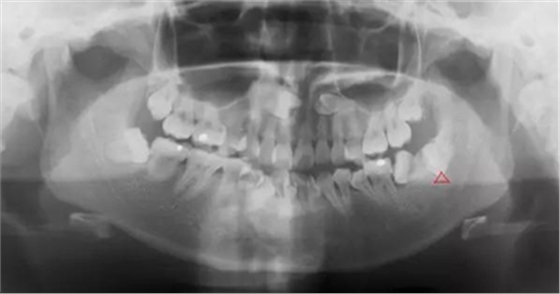

熟悉牙體牙周解剖形態(tài),設(shè)計拔牙手術(shù)方案,評估牙齒脫位道及周圍軟硬阻力,控制用力大小和方向,避免周圍組織以及對合牙齒的損傷,考慮如何用最小的力,最小的拔牙創(chuàng)傷,最短的時間拔除患牙。拔牙時先將牙齒進行分割后使用微創(chuàng)拔牙器

械,輕輕地插入需要拔除的牙齒周圍,切斷相互連接的牙周韌帶,使牙齒充分松動并輕松脫出。微創(chuàng)拔牙要求無痛局部麻醉,追求零敲擊、小創(chuàng)傷理念,利用各種微創(chuàng)器械,對術(shù)區(qū)組織進行嚴格的保護,達到創(chuàng)傷最小化。患者拔牙時更加舒適,使拔

智齒水平阻生(長橫過來了),影響前面牙齒或者致前面牙齒擁擠不齊

智齒遠中阻生(遠離鄰牙方向長)反復(fù)炎癥感染

1.水平阻生影響前牙